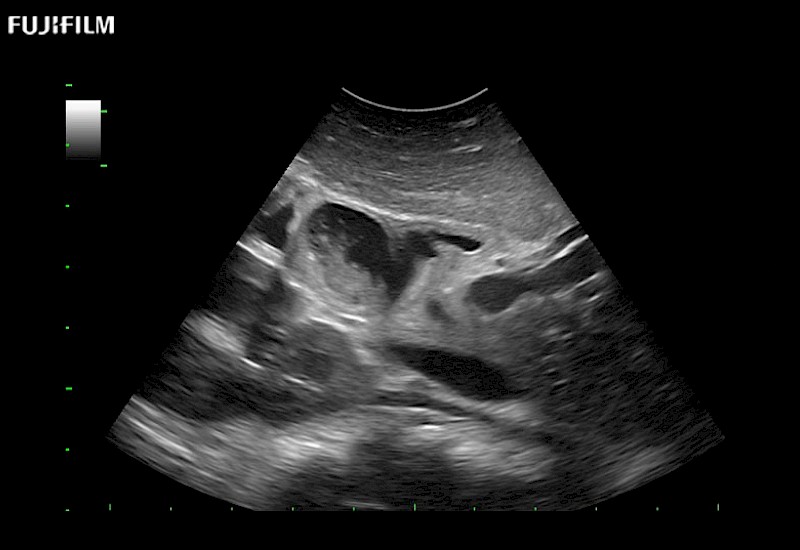

for use during open and laparoscopic procedures: Tumor localization & staging, Ablation, Resection, Biopsy, Transplant, Abdominal exploration, Robotic surgery

Our dedication to Surgical Oncology allows us to offer superior image quality, outstanding system reliability and intuitive use of cutting edge technology.